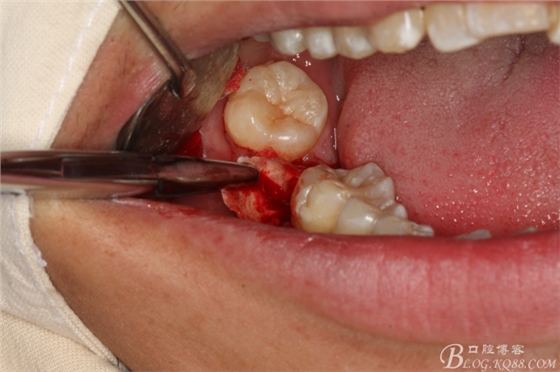

圖16.挺出47牙根

圖17.持針器牽引出47牙根

圖18.牙根取出后,牙槽窩形狀未改變

圖19.牙槽窩放膠質(zhì)銀止血海綿